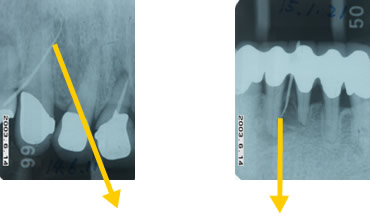

治療例

排膿している歯ぐきの孔に探索用ゴムを挿入し原因部を特定(歯根の先に至る)

歯の中の神経が感染した部分を掃除後、神経が入っていた部分を密閉